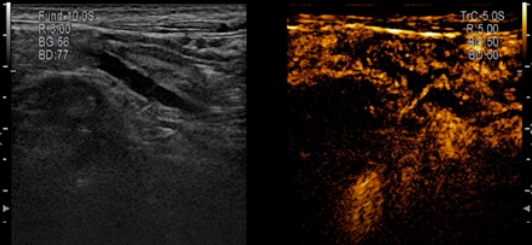

近日,首都医科大学附属北京中医医院超声科联合消化科,在中国超声医学工程学会胃肠超声专家指导下,成功完成5例炎症性肠病患者肠道超声造影检查。超声检查结果与患者病情相符合,为后续治疗决策提供重要的依据。

随着超声新技术层出不穷,超声造影在炎症性肠病上的应用得到国内外学者的广泛关注。大量研究已经证实超声对炎症性肠病患者的诊断、病情评估、定期随访及治疗方案的制定方面具有重要的临床价值。

肠道超声造影检查与常见的甲状腺、乳腺超声造影一样,是通过外周静脉注入造影剂,观察病变部位肠道的层次结构、肠腔有无狭窄、肠壁微血流灌注情况及肠道周围爬行脂肪及淋巴结情况,为临床对炎症性肠病的诊治提供参考依据。同时也拥有五大优势:

3.  可以显示微血流灌注情况,评估患者是否处于活动期。